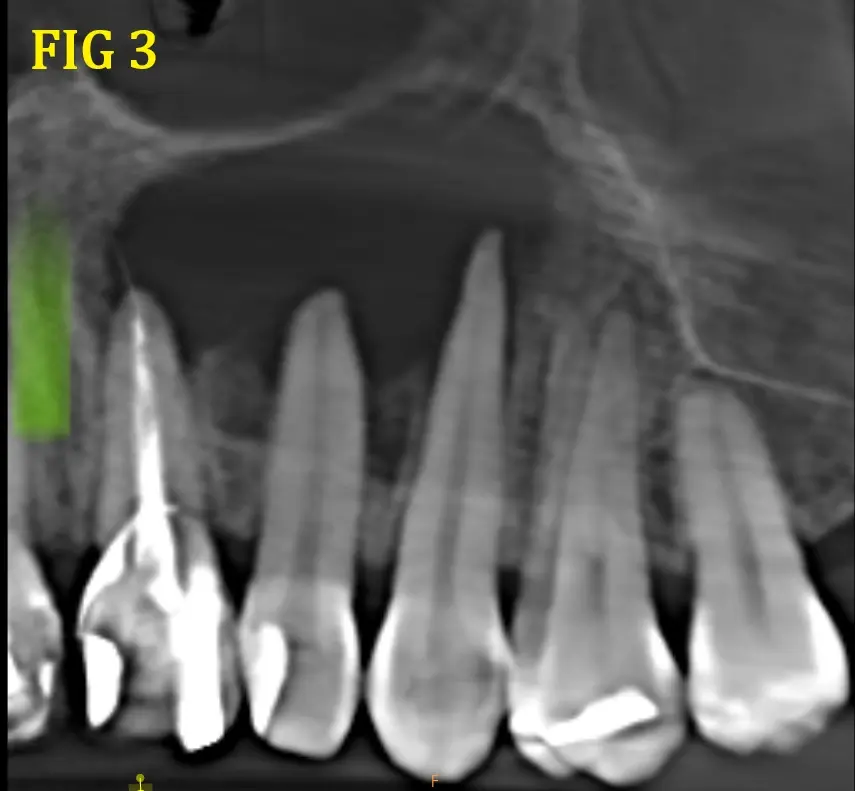

Al realizarle la tomografía se observó una imagen hipodensa (Fig. 1 y 2) proveniente de la pieza dental 21, pieza en la que fue realizada un tratamiento de conducto, donde se llega a observar una sobre obturación (Overfilling) (Fig. 3 y 4), el material hiperdenso se observa sobresalir del ápice radicular sobrepasando el limite CDC (conección Dentino-Cementaria) , generando el quiste periapical. ( Fig. 5). El quiste va generando presion a las piezas adyacentes y se extiende desde pieza dental 21 a 23 inclusive.

Se describe la tipica imagen expansiva sobre los tejidos scircundantes, tipo globo con agua, que tiene limites bien definidos, aunque por su tamaño y posibles reagudizaciones en algunas zonas se encuentra ausente o cueste distinguirlo, provocando ensanchamiento de las tablas libres y adelgazamiento